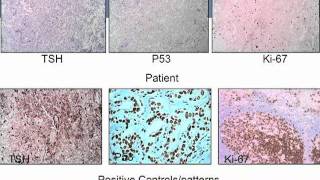

Clinical History - Stalk Effect | UCLA Pituitary Tumor Program Surgical Pathology - Stalk Effect | UCLA Pituitary Tumor Program

Surgical Pathology - Stalk Effect | UCLA Pituitary Tumor Program Post-Operative Course - Upfront Radiosurgery | UCLA Pituitary Tumor Program

Clinical History - Stalk Effect | UCLA Pituitary Tumor Program Surgical Pathology - Stalk Effect | UCLA Pituitary Tumor Program

Surgical Pathology - Stalk Effect | UCLA Pituitary Tumor Program Post-Operative Course - Upfront Radiosurgery | UCLA Pituitary Tumor Program